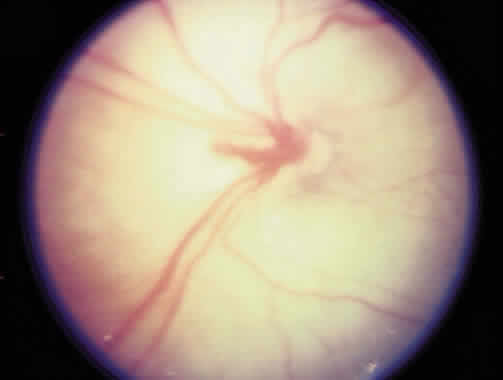

Laser is particularly useful in the management of zone I and posterior zone II disease. Most often, conjunctival incisions are necessary to get a cryotherapy probe posterior enough to treat zone I disease. This problem is obviated with laser delivery. Results of treatment of zone I disease in the Cryo-ROP Study are poor, whereas success rates of 80% to 90% have been reported in managing zone I disease with laser.71, 72, 73, 74, 75 Ridges in zone I or posterior zone II disease often are wider, with more defined vasculature than in zone II disease (Fig. 9). Zone I disease can be determined with a + 25 D lens. The disc is visualized at one rim of the lens, and avascular retina can be seen at the opposite rim when zone I disease is present (Fig. 10). A This occurs at a significant rate in the eyes of the smallest infants (500 g) with a gestation of 22 to 26 weeks. There may be an associated persistence of fetal vasculature (Fig. 11).

Fig. 9. Zone I retinopathy of prematurity with a flat ridge.

Fig. 10. Zone I retinopathy of prematurity determined with a + 25 D lens. The optic nerve is seen at the 9-o'clock position on the rim of the lens and avascular retina at the 1- to 5-o'clock positions on the rim of the lens.

Fig. 11. Persistent fetal vessels in a premature infant of about 24 weeks' gestation.